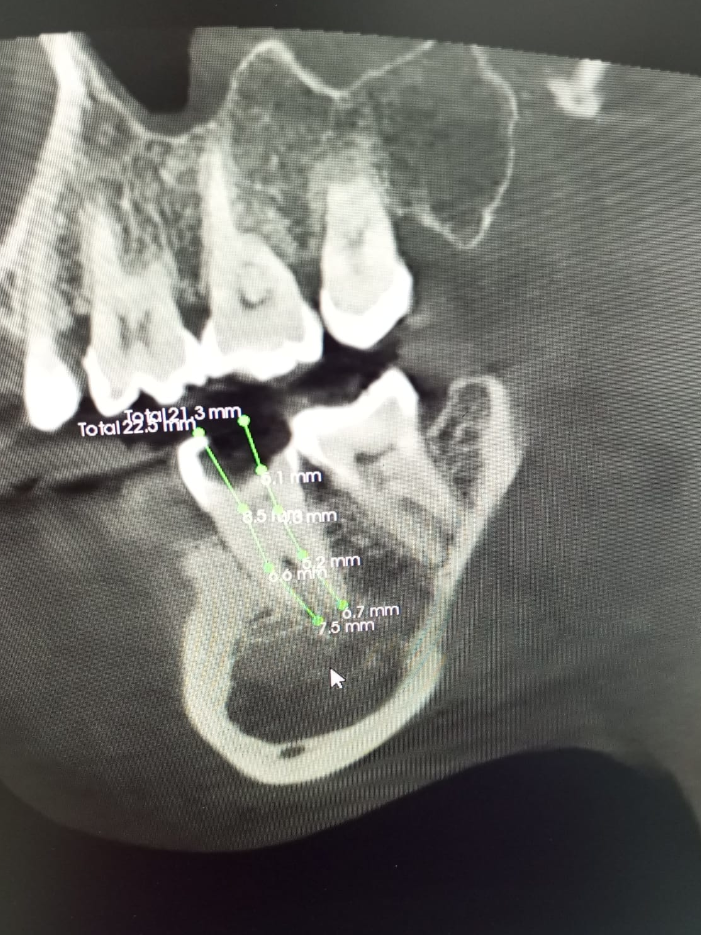

Galería

Algunos de nuestros tratamientos de endodoncia que permiten salvar piezas dentales, eliminar infecciones y devolver la salud y funcionalidad a tu sonrisa.